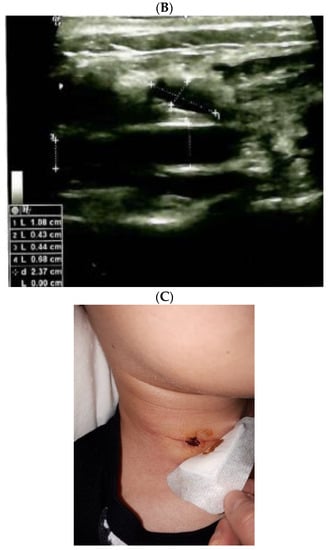

The diagnostic of HS was established after she was seen by different specialists as outpatient; she started local therapy with artificial tears and local nasal products with no significant improvement. In the meantime, a right neck swelling was progressively increasing, thus she was re-admitted 5 weeks since thyroidectomy. Neck ultrasound revealed a hypoechoic cystic-like area at the level of right lateral cervical level (of 60 mm maximum diameter) without thyroid remnants or local lymph node enlargement. (Figure 2).

Figure 2.

Neck ultrasound (right lateral area): hypoechoic, cystic- like, well-shaped mass of 6 by 2 by 4.5 cm (post-thyroidectomy capture: after 5 weeks since surgery before any additional intervention; red line represents the limits of the mass).

Ultrasound—guided fine need aspiration of the right mass provided cvasi-complete reduction of the liquid with stationary ultrasound features after 90 min. The liquid examination showed mature lymphocytes, rare erythrocytes, rare cholesterol crystals, lymph fluid, consistent with the diagnostic of lymphocele. A mild clinical improvement of HS—associated features was registered, but within 2 days, the neck mass rapidly regrew, and the patient was re-admitted. Under local anesthesia, there was a liquid evacuation (macroscopic aspect with milky-like aspect, a volume of 5–6 mL) and a drain tube was placed for 4 days. Ultrasound aspects showed a progressive regression of the right cystic mass with improvement of HS which slowly remitted within the next 2–3 months. (Figure 4).

Figure 4.

The evolution of within following weeks after thyroid surgery ultrasound features. (A). Right neck ultrasound aspect at the moment of fine needle aspiration (5 weeks since surgery)—on the right and 6 days after fine needle aspiration procedure (after cvasi-complete evacuation, the cystic mass relapsed within 48 h)—on the left. (B). Right neck ultrasound within the first day of tube drainage (6 weeks since initial surgery) showing a massive reduction of the cystic mass. (C). Drainage tube was removed after 4 days. Post-thyroidectomy scar and post-tube removal aspect. (D). Right neck ultrasound after 2 weeks from removing the drainage—persistent cystic mass, but with progressive improvement of HS (approximately 9 weeks since initial surgery). (E). Right neck ultrasound after another 2 weeks from removing the drainage –progressive reduction of cystic mass, but with remarkable improvement of HS (approximately 11 weeks since initial surgery). (F). Scar aspect 12 weeks since surgery and 5 weeks since lymphocele drainage. (G). Recovery of HS—approximately 8 weeks since drainage. (H1,H2). Bilateral neck ultrasound 20 weeks since thyroid surgery showing regression of the lesions on both sides versus prior examinations. (H1). Right later-cervical cystic collection of 2 by 2.8 by 0.9 cm (2.5 mL) and peripheral areas of fibrotic reorganization. (H2). Left later-cervical hypoechoic, inhomogeneous mass (no vascular signal) showing fibrotic reorganization (0.25 mL).